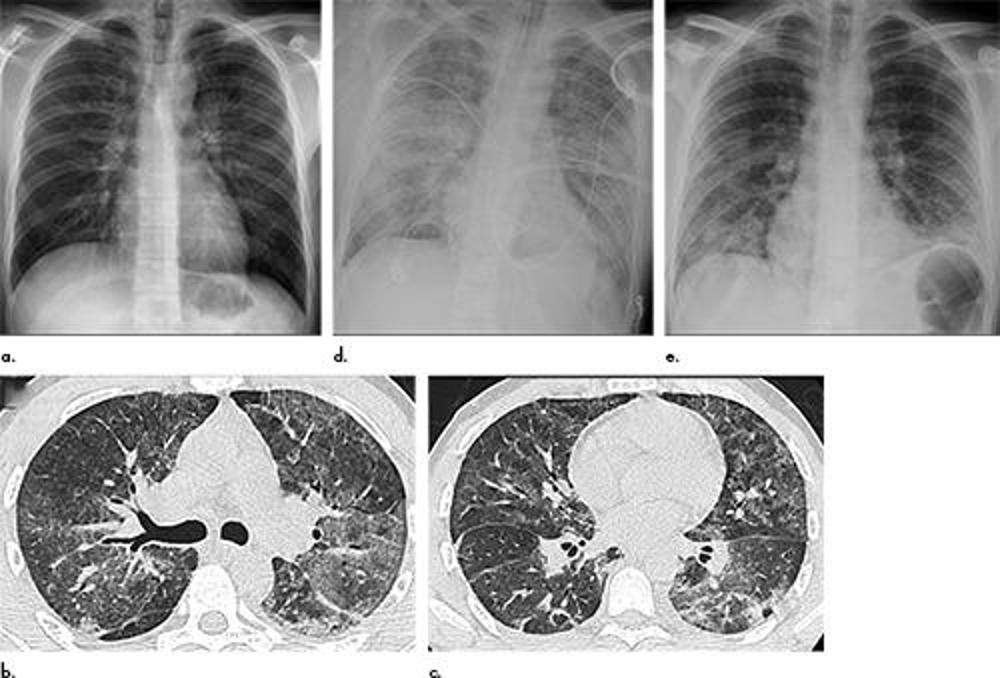

Figure 1. Electronic cigarette or vaping product use–associated lung injury in a 51-year-old man manifesting as an acute lung injury pattern at CT with subsequent organization. (a, c) Axial unenhanced CT images at presentation through (a) mid and (c) lower lungs show ground-glass opacity with subpleural sparing (arrows); this distribution was present in 45% of chest CT studies at presentation in our cohort (11). (b, d) Axial unenhanced CT images obtained 6 days later show ground-glass opacity has transitioned to consolidation and mild architectural distortion, consistent with developing organization. The patient was initially treated with antibiotics followed by corticosteroid therapy, with slow clinical improvement.

Figure 2. Electronic cigarette or vaping product use–associated lung injury in a 27-year-old man manifesting as an acute lung injury pattern at CT but showing diffuse alveolar damage at surgical biopsy. (a) Frontal chest radiograph at presentation shows faint bilateral perihilar poorly defined bronchovascular bundles best seen involving the left hilum. (b, c) Axial unenhanced CT images through the (b) mid and (c) lower lungs obtained 2 days after presentation show multifocal bilateral ground-glass opacity and consolidation, without a clear zonal predilection. (d) Frontal chest radiograph obtained 6 days after presentation, following the development of hypoxic respiratory failure, shows worsening bilateral opacities. (e) Final chest radiograph 20 days following presentation shows that the bilateral lung opacities have improved significantly, but residual abnormalities remain.